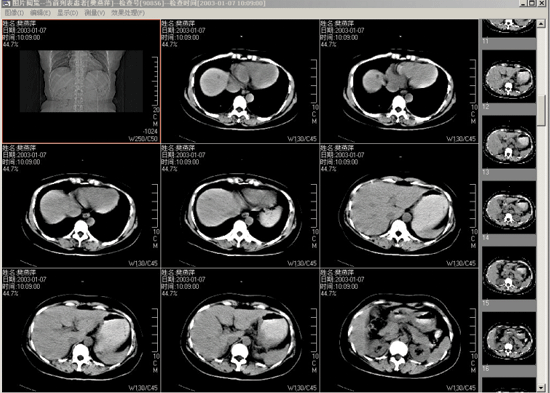

影像浏览和诊断子系统

□ 影像显示:DICOM3.0、BMP、JPEG等格式图像的导入/导出,显示设置、显示模式、图像放大/缩小、移动、镜像、反相、旋转等

□ 影像处理:窗宽、窗位调节、滤波、边缘增强、伪彩、剪影、锐化/柔化等

□ 辅助测量:CT值曲线、CT、MR值测量,直线测量,角度测量,面积极值和均值测量